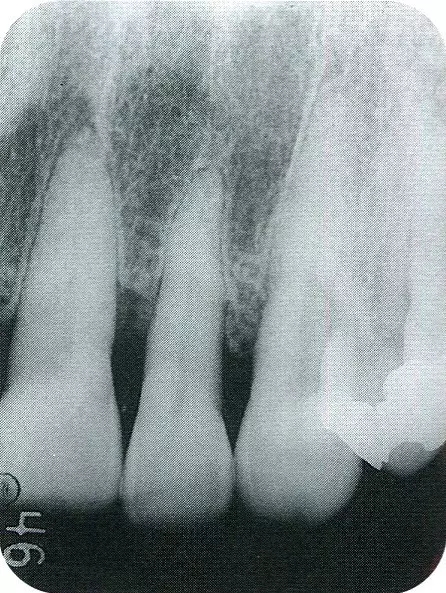

▲圖7-2  術(shù)前x片。確認存在垂直性深骨缺損。